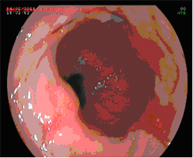

Diagnosis is performed using high-resolution magnification endoscopy (image enhancement), employing additional chromoendoscopy techniques conducted by endoscopists specialised in the early diagnosis of premalignant lesions, with targeted biopsies for analysis.

Endoscopic mucosectomy

Endoscopic mucosal resection involves the endoscopic removal of a section of the mucosa and submucosa (in this case of the oesophagus). It is indicated whenever elevated lesions are observed in Barrett's oesophagus during diagnostic endoscopy.